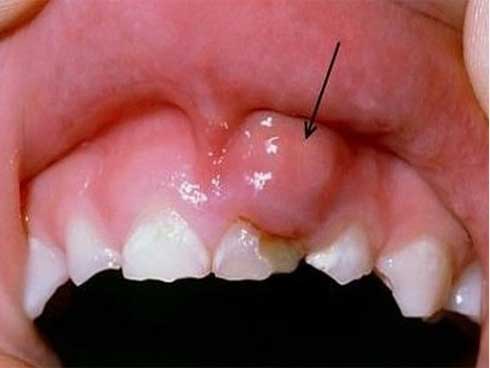

Tổn thương sùi: thường là những nụ nhỏ, gồ, như hình súp – lơ, có thể kết hợp tổn thương loét, chảy máu.

Do tổn thương thực thể chủ yếu là tổn thương sùi, loét, chảy máu… Nên người ta khuyến cáo với những người có tổn thương loét dù nhỏ mà tồn tại ở 1 vị trí cố định trên 1 tháng là có chỉ định sinh thiết để xác định bản chất tổn thương.